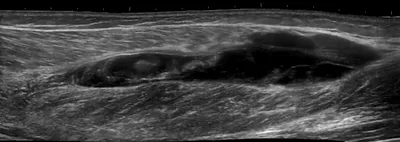

This collection contains 1 radiology images related to calf, including various imaging modalities such as X-rays, MRIs, CT scans, and ultrasound images commonly used in medical diagnosis and education.